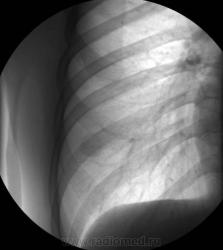

ПРицельная рентгенограмма правого легкого. Ваше мнение?

Если Вы о тени соска, Виталий, то отвечу сразу - это не он и слева такого нет, хотя ход Ваших мыслей абсолютно правильный.

Кстати....это барышня.....средних лет и достаточно худая....

Много чего "всякого - разного" может дать такую тенюху. Рискну - периферический, гамартома, аретерио-венозная аневризма.

а может образование в молочной железе

Аризона - Вы умница!!!